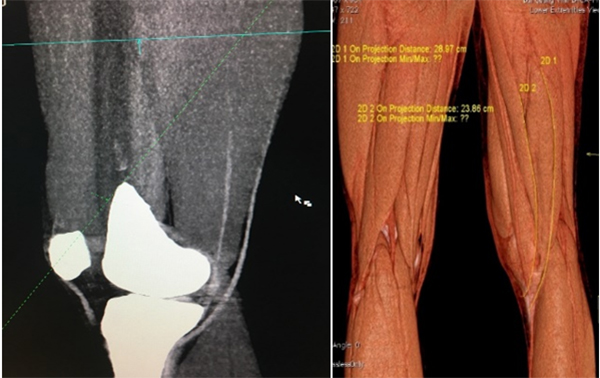

| Hình ảnh dựng hình 3D trên CLVT đo kích thước gân trước mổ. |

Trước đây, việc dự đoán kích thước gân cơ thon và bán gân dựa trên kinh nhiệm của phẫu thuật viên, thường không chính xác. Cùng với xu hướng y tế ngày càng phát triển, điều trị trên từng bệnh nhân cụ thể thì phương pháp đánh giá trước kích thước gân cơ thon và bán gân bằng chụp CLVT dựng hình 3D là một bước thiết yếu trước phẫu thuật, cung cấp thông tin cho bác sĩ quyết định lấy một hay cả 2 gân, lựa chọn phương pháp mổ (đặc biệt khi chọn kỹ thuật mổ 2 bó với mục đích muốn phục hồi tối đa giải phẫu cũng như chức năng của DCCT nguyên bản) nhằm tối ưu hóa kết quả phẫu thuật, đảm bảo kết quả cao nhất bệnh nhân là các vận động viên, cán bộ chiến sỹ lực lượng vũ trang.